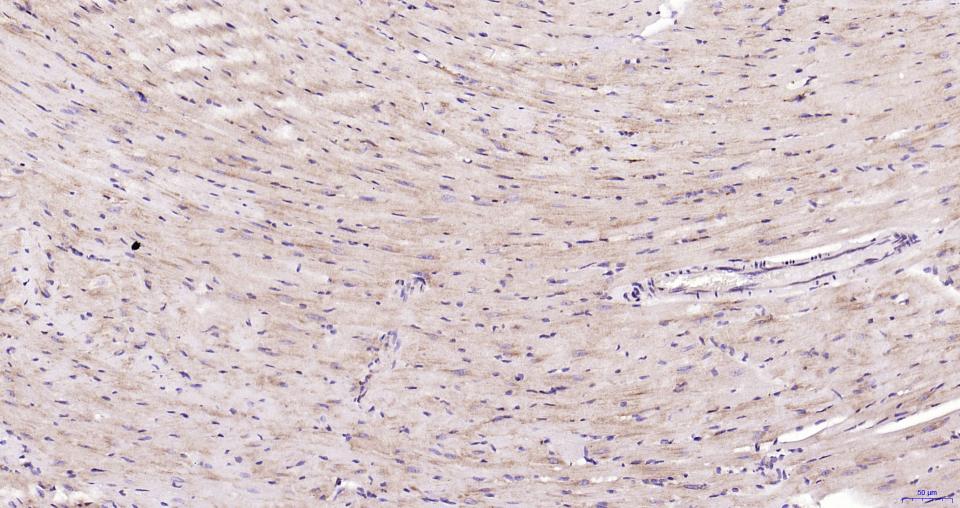

Cardiovascular > Heart > Cardiac metabolism

| IHC-P | Human, Mouse, Rat | 1:200-1000 | |